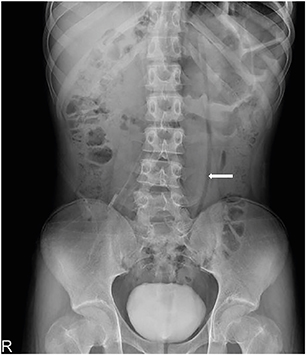

A previously healthy 16-year-old boy with stable vital signs presented with vomiting, diarrhea, distension, and abdominal pain for 4 days. On physical examination, he had abdominal distension with mild abdominal tenderness but without rebound tenderness, and a subtle metallic bowel sound. Laboratory test results were normal. An abdominal radiography revealed a dilated sigmoid colon on the left quadrant (Fig. 1). An abdominal computed tomography (CT) revealed a marked distension of the gas-filled sigmoid colon with twisting of the mesenteric vessels, confirming SV (Fig. 2). A rectal tube was inserted to decompress the volvulus (Fig. 3). He remained asymptomatic thereafter, and discharge was requested. At 2 and 7 months after his initial attack, he was readmitted to the emergency department with the same complaints. Subsequent examinations confirmed the recurrence of SV. The SV was successfully decompressed by means of a rectal tube. His parents again refused surgical treatment; however, 9 months after the first attack, he underwent laparoscopic-assisted sigmoid colectomy. We use a 12 mm port above the umbilicus, a 5 mm right upper quadrant port, a 5 mm left sided port, and a 12 mm right lower quadrant port & left lower quadrant, typically placed 2 fingerbreadths medial and 2 fingerbreadths cephalad to the anterior superior iliac spine. After mobilization of the sigmoid colon, the colon was transected at the rectosigmoid junction with an endolinear stapler (SigniaTM Stapling System; Medtronic, Minneapolis, MN, USA). The umbilical incision was extended. The divided sigmoid colon was exteriorized, and the redundant part was resected. A sigmoid colon section of 34 cm was resected; end-to-end colorectal anastomosis was performed intracorporeally using a circular stapler (ECHELON CIRCULARTM 25 mm Powered Stapler; Ethicon, Bridgewater, NJ, USA). A seromuscular biopsy specimen from the distal colon submitted for histopathologic examination showed normal ganglion cells. On postoperative day 3, he was started on water intake; subsequently, eating progressed successfully. He was discharged without complications on postoperative day 10.

Fig. 3

Abdominal X-ray showing decompression of the volvulus by means of a rectal tube (arrow).